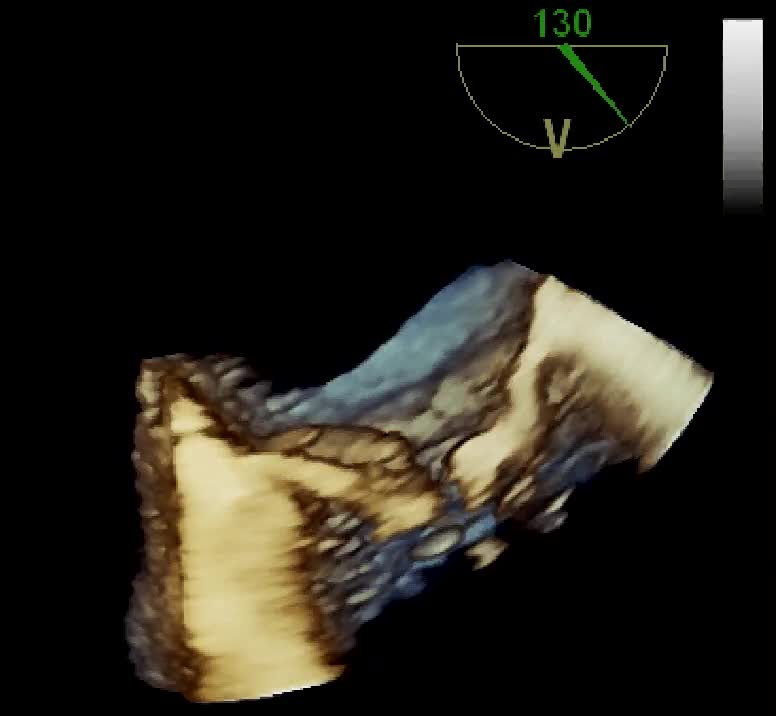

Insufficienza mitralica da rottura cordale

Autore:

Daniela Torta